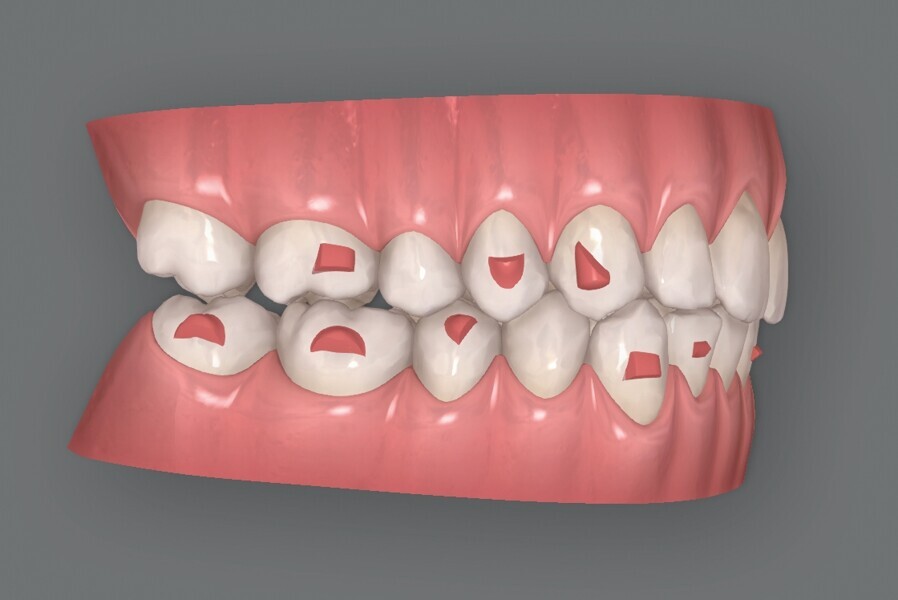

Fig. 5a : Plan supplémentaire du traitement par aligneurs conçu par ClinCheck (début).

Fig. 5b : Plan supplémentaire du traitement par aligneurs conçu par ClinCheck (début).

Fig. 5c : Plan supplémentaire du traitement par aligneurs conçu par ClinCheck (début).

Figs. 5d : Plan supplémentaire du traitement par aligneurs conçu par ClinCheck (début).

Fig. 5e : Plan supplémentaire du traitement par aligneurs conçu par ClinCheck (début).

La première série d’aligneurs permet de réaliser les mouvements orthodontiques programmés dans le logiciel avec une efficacité supérieure à 95 % (Fig. 5), et d’obtenir une forme anatomique des arcades, une correction de l’occlusion croisée et de la relation de classe II du côté gauche, une réduction de l’encombrement dans le maxillaire et la mandibule, et un alignement des lignes médianes. Au terme de cette première phase, les observations cliniques indiquent une infraclusion postérieure, résultant de l’intrusion passive des dents postérieures due à l’épaisseur du matériau de l’aligneur, et des contacts antérieurs prématurés. Quelques mouvements dans la zone incisive mandibulaire sont encore nécessaires pour terminer le traitement, et un deuxième jeu d’aligneurs est donc prévu pour éliminer les problèmes et finaliser la position des dents.